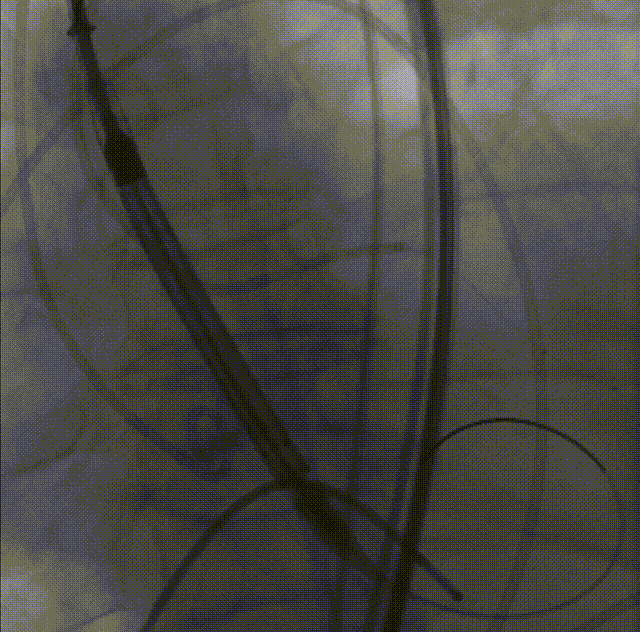

26VenusAplus+snare

瓣膜内22mm球囊后扩张,左冠无显影

LM烟囱支架植入4.0*30mm